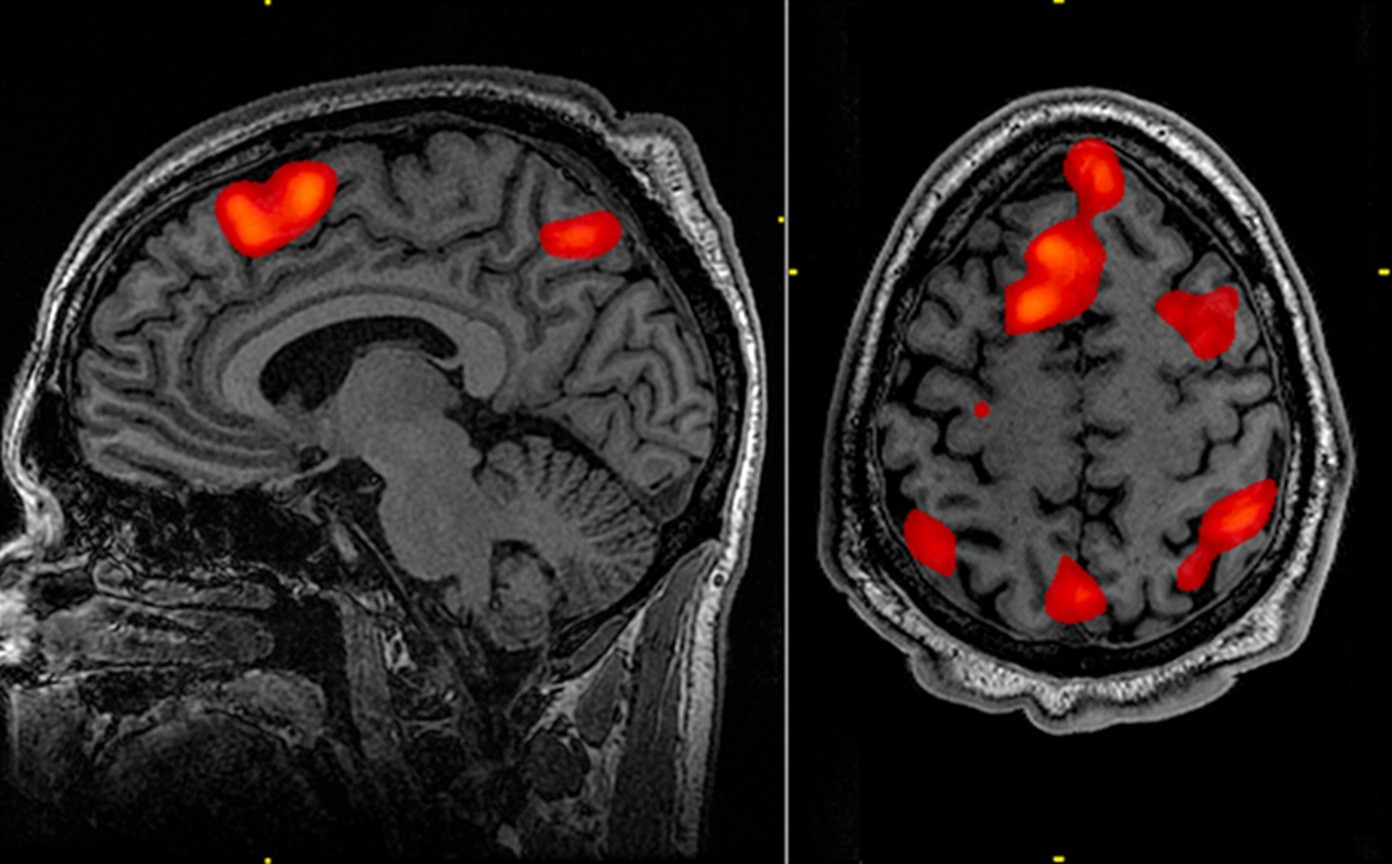

A doença de Huntington, uma condição neurodegenerativa rara, mas cruel e devastadora, foi tratada com sucesso pela primeira vez.

A doença de Huntington é causada por uma mutação no gene da huntingtina, que leva à produção de uma proteína tóxica para os neurônios. A condição provoca perda progressiva de funções motoras, cognitivas e comportamentais, resultando em dependência e morte, geralmente em até 20 anos após o início dos sintomas.